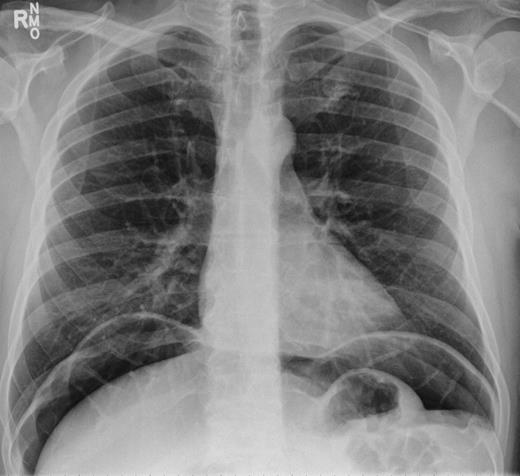

In 2011, a 46-year-old man presented with an acute abdomen. Patient had a 3 day history of abdominal pain with dyspepsia, initially epigastric with pain radiating to his shoulder. He had no associated symptoms of nausea, vomiting or change in bowel habit. There was no history of peptic ulcer disease, inflammatory bowel disease, diverticular disease or malignancy. His pain was refractory to standard analgesics and exacerbated by movement and palpation of the abdomen. There was no past medical or family history of note, and the patient had never experienced these symptoms before. Routine observations were normal, except for tachycardia. On examination, there were no peripheral stigmata of inflammatory bowel disease, abdomen was diffusely tender and tympanic, but soft with normal bowel sounds. Blood tests showed no significant abnormalities, and C-reactive protein (CRP) levels were not measured. Plain abdominal and erect chest radiographs showed pneumoperitoneum (Fig. 1) with Rigler's sign present around small bowel loops lower in the abdomen (Fig. 2).